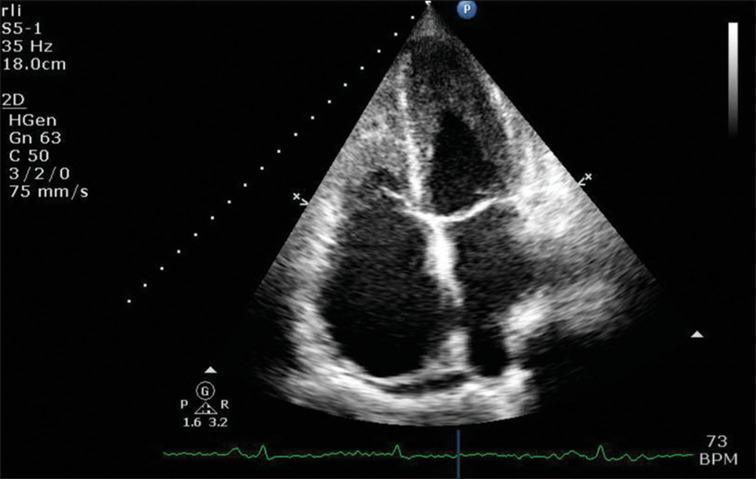

Loeffler first described "fibroplastic parietal endocarditis with blood eosinophilia" in 1936. This we now know refers to the most common cardiac manifestation of an uncommon condition, the so-called hypereosinophilic syndromes. This condition typically results in a restrictive cardiomyopathy affecting the left heart, but here, we present an unusual case of a 65-year-old woman with chronic hypereosinophilia of at least 2 years, who presented with right heart failure as a result of eosinophilic endomyocardial infiltration of her right ventricle. We explore the diagnostic pathway and look at the literature on management.

勒夫勒于1936年首次描述了“伴有血液嗜酸性粒细胞增多的纤维增生性心内膜炎”。我们现在知道,这指的是一种罕见病症(即所谓的嗜酸性粒细胞增多综合征)最常见的心脏表现。这种病症通常会导致影响左心的限制性心肌病,但在此,我们报告一例不寻常的病例,一名65岁女性,患有至少2年的慢性嗜酸性粒细胞增多症,因右心室嗜酸性粒细胞性心肌内膜浸润而出现右心衰竭。我们探讨了诊断途径并查阅了有关治疗的文献。